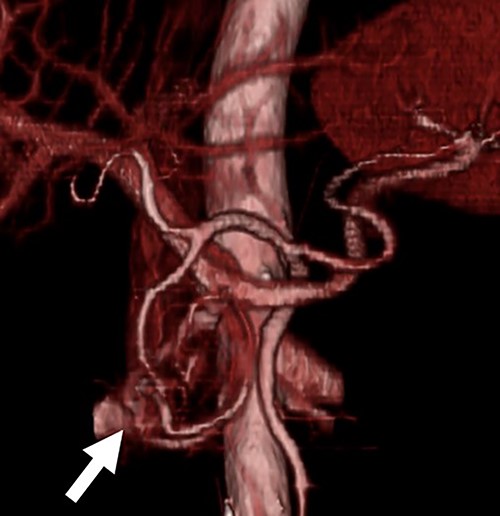

Three-dimensional CT image. The three-dimensional CT imaging showed the communication between arteries and veins in the pancreatic head (arrow).